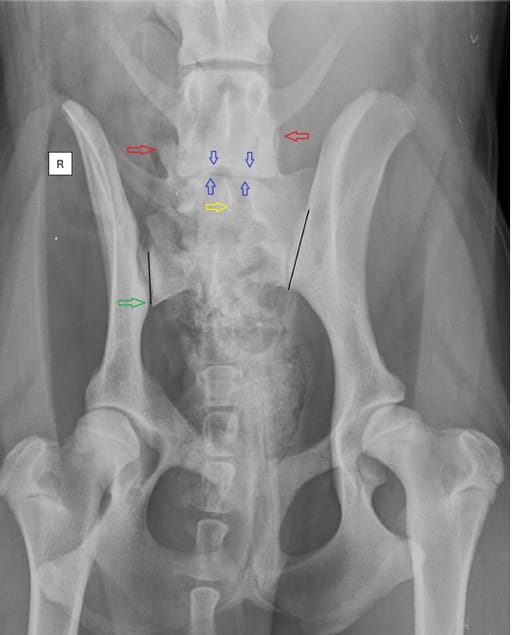

Ventrodorsal radiography with extended hips reveals an asymmetric lumbosacral transitional vertebra (LTV). The lumbosacral transitional vertebra

(LTV) segment exhibits a sacral-like transverse process with a broad contact area on the left. The rotation of the LTV segment is evident on both the verticalmand longitudinal axes, leaning towards the left. This is observed through the spinous process (yellow arrow), cranial articular facets (red arrows), and cranial and caudal endplates compared to the last normal lumbar vertebra (blue arrows). The pelvis demonstrates longitudinal axis rotation, noticeable in the wider left iliac wing and the asymmetric appearance of the obturator foramen. Additionally, a counterclockwise vertical rotation of the pelvis and sacrum is observed and a caudal displacement of the sacroiliac joint (green arrow). This displacement shortens the distance from the sacroiliac joint to the hip joint on the right side. Moreover, inadequate coverage of the left acetabulum leads to subluxation of the left hip joint. Axial malpositioning of a normal dog during the radiographic examination results in apparent rotation of the pelvis and the caudal lumbar spine in the same direction. However, if the direction or degree of the rotation, or both together, between the pelvis and lumbar spine are different, an inherent malposition should be considered [8]. The black lines demonstrate the measurement of the sacroiliac joint length. (The radiograph is for illustration purposes and not from the NKK database)